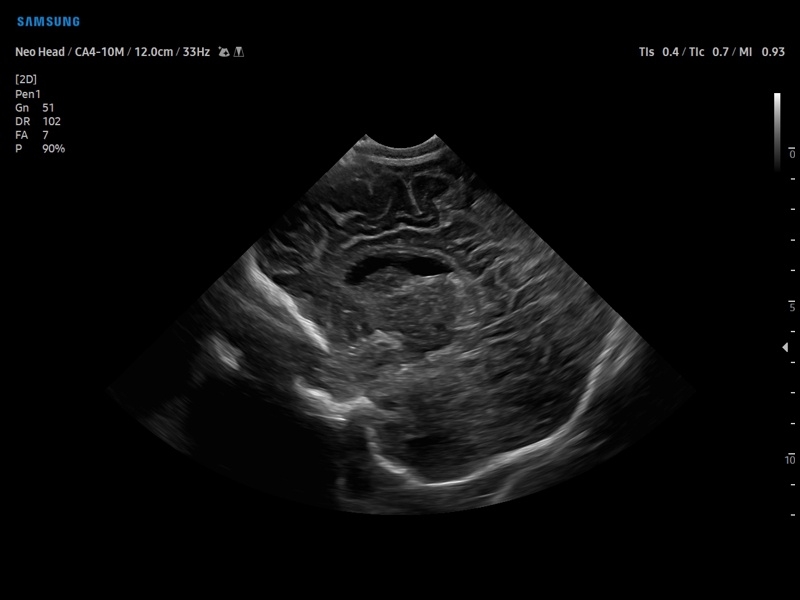

Ультразвуковой сканер V8-RUS является экспертным классом (премиальный уровень) и производится компанией Samsung Medison. Сканер V8 обеспечивает превосходное качество изображения благодаря использованию технологии Crystal Architecture™, которая включает в себя передовое аппаратное обеспечение, монокристальную технологию изготовления датчиков и сложную программную обработку ультразвуковых лучей.

• Педиатрия и неонатология

• Транскраниальные исследования